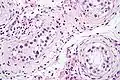

-

ITGCN. H&E stain.

GCNIS is not palpable, and not visible on macroscopic examination of testicular tissue. Microscopic examination of affected testicular tissue most commonly shows germ cells with enlarged hyperchromatic nuclei with prominent nucleoli and clear cytoplasm. These cells are typically arranged along the basement membrane of the tubule, and mitotic figures are frequently seen. The sertoli cells are pushed toward the lumen by the neoplastic germ cells, and spermatogenesis is almost always absent in the affected tubules. Pagetoid spread of GCNIS into the rete testis is common. Immunostaining with placental alkaline phosphatase (PLAP) highlights GCNIS cell membranes in 95 percent of cases. OCT3/4 is a sensitive and specific nuclear stain of GCNIS.[3]